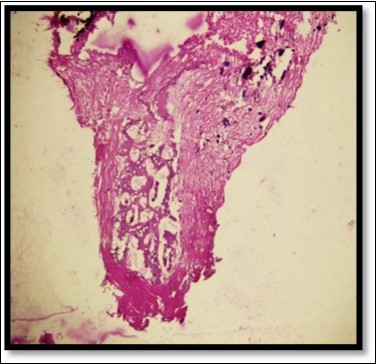

During the next visit local anesthesia was given. The lesion was excised with the help of soft tissue laser and sent for histological examination. (Figure 2) Histological report confirmed the lesion is Peripheral cemento-ossifying Fibroma. Histological analysis showed lesional tissue comprising of both trabecular bone and woven bone. Periphery of the lesion showed numerous globular and irregular cementum like calcification. In most areas these calcification coalesced with each other forming bigger calcification. The supporting connective tissue stroma was loose fibrillar with less cellularity. Detached overlying parakeratinized epithelium was observed in one area. (Figure 3) Post operative evaluation revealed normal healing after one month. (Figure 4)

Figure 3.Histologically H & E stained section shows trabecular bone and woven bone more towards the center of the lesion

Histologically, PCOF shows a parakeratinized and hyperplastic epithelium and well-cellularized connective tissue containing mineralized components ranging from bone to cementum and, less frequently, dystrophic calcifications.11 Histopathological examination is essential to confirm the diagnosis of PCOF, since clinically it resembles a pregnancy tumor, epulis fibrosa, inflammatory hyperplasia, or peripheral and central giant cell granuloma.3